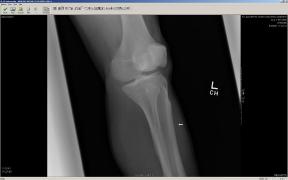

X-Rays Following Hyperextension of Left Ankle (January 31st 2006)

These x-rays were taken following a fluke event where Liam hyperextended his left ankle while playing an XBox 360 video game. As can be

seen in the images there are two (2) breaks that were produced from the hyperextension. One of the tibia bones has a hairline break and

the bone piece that spontaneously fused the tibia to the fibula has snapped. It took almost 2 weeks to determine that these breaks had

occurred. Due to Liam’s unique pain threshold and the lack of visible indicators, a break was not considered. Just another senseless

accident that resulted from the use of a violent video game. ;-) Yeah, right...